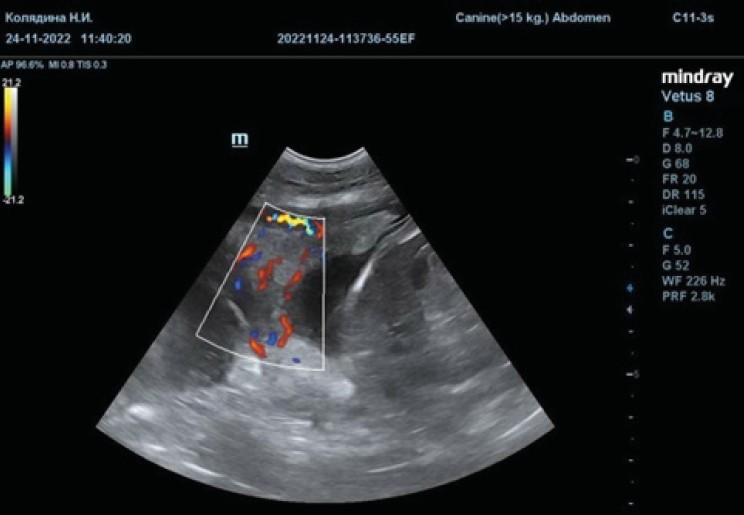

Fig. 8. Ultrasound imaging of placental vessels in the CDI mode in a Boston Terrier female

Source: compiled by N.I. Kolyadina, A.V. Shumeyko on the Mindray Vetus 8 Ultrasound Machine.

Source: compiled by N.I. Kolyadina, A.V. Shumeyko on the Mindray Vetus 8 Ultrasound Machine